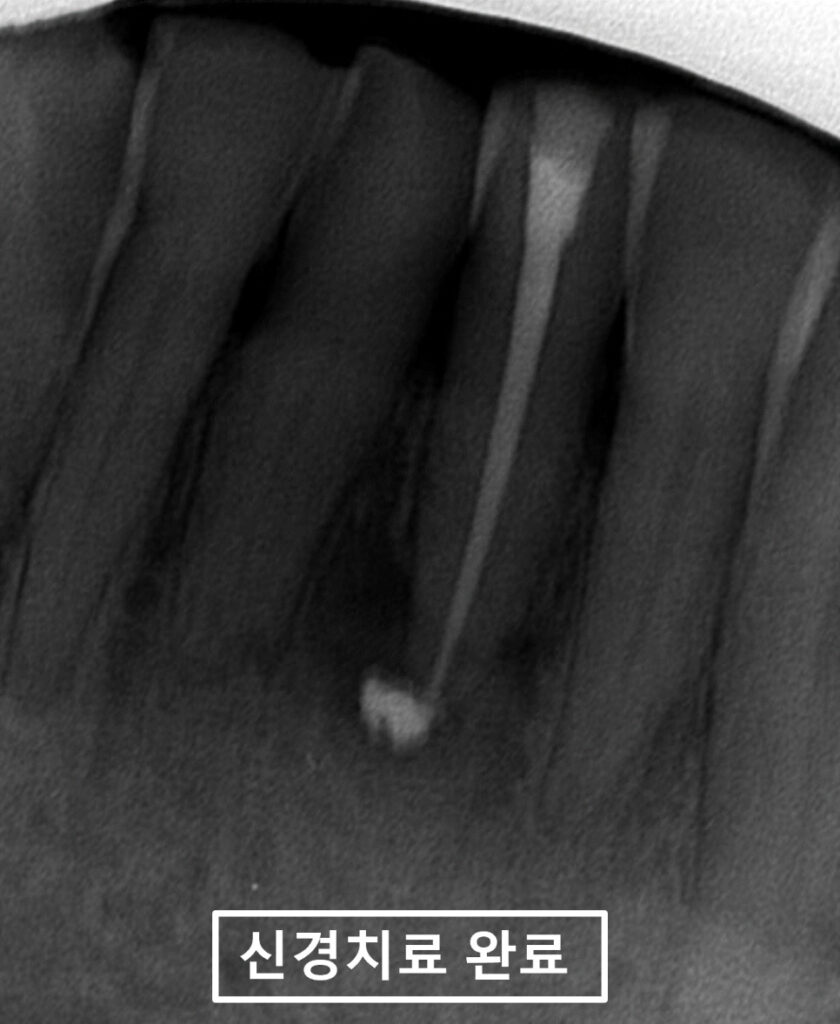

신경치료를 2회에 걸쳐 마무리를 하고,

촬영한 x-ray 사진입니다.

앞니통증은 모두 사라졌고,

환자분도 굉장히 편안한 상태에서

진료가 마무리 되었습니다.